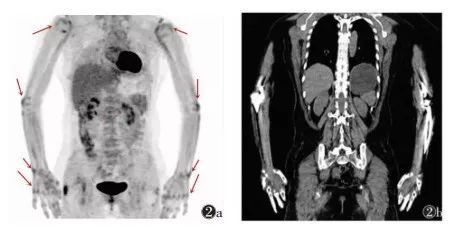

PET\/CT-MR 异机融合

554x326 - 259KB - PNG